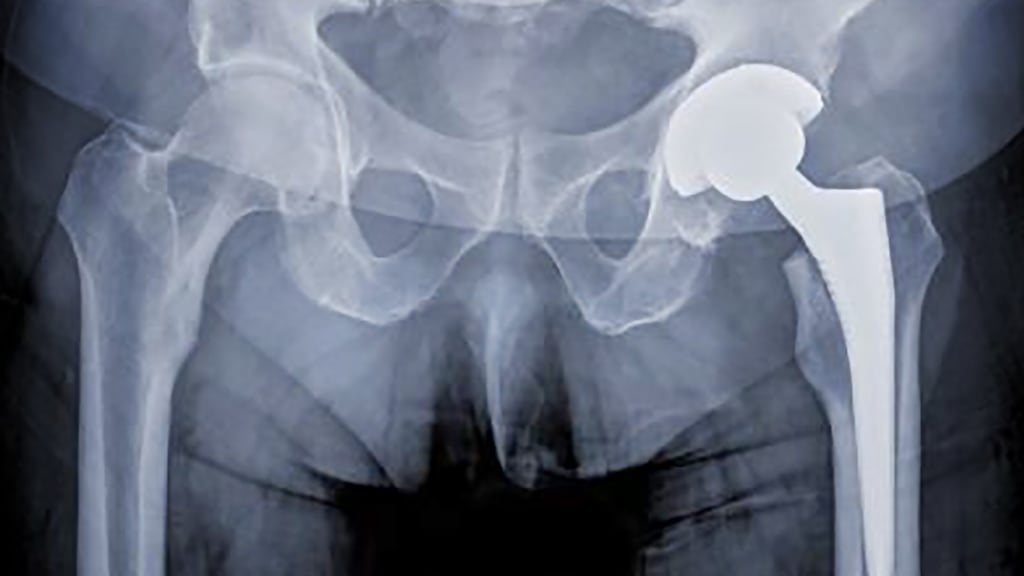

In August 2010, DePuy Ireland Unlimited announced a world-wide voluntary recall of certain products used in hip replacement surgery.

In Ireland, about 3,300 patients received these implants, across 16 public and 14 private hospital sites nationwide.